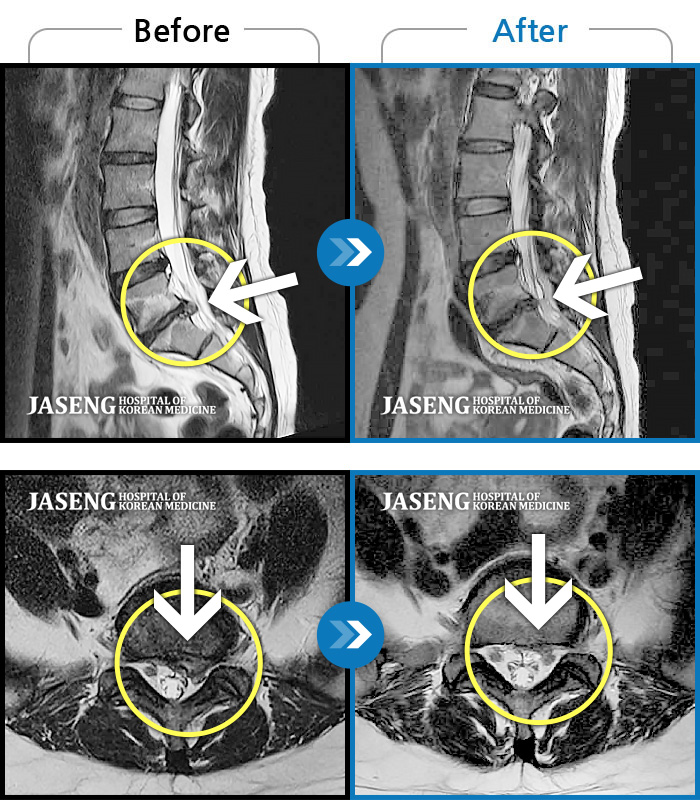

허리디스크

잠실 · 한상욱 원장

우측 엉치부터 우측 다리부터 발끝까지 저리고 아프다. 감각까지 먹먹하다.

촬영시기

2022.04.15 ~ 2022.10.22

2022.12.02